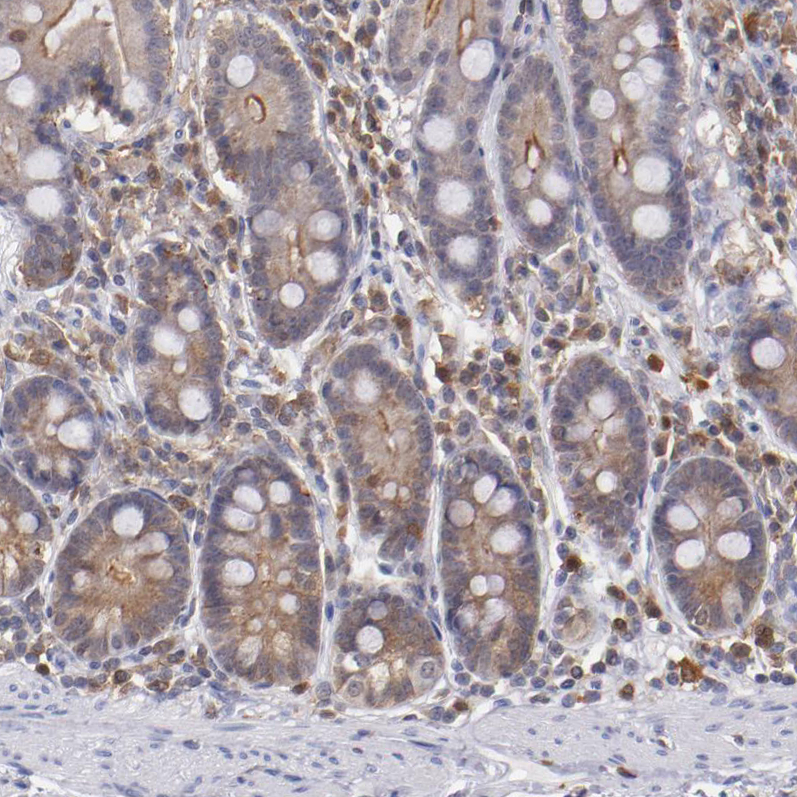

Immunohistochemistry analysis in human tonsil and skeletal muscle tissues using HPA001890 antibody. Corresponding PRKCD RNA-seq data are presented for the same tissues.